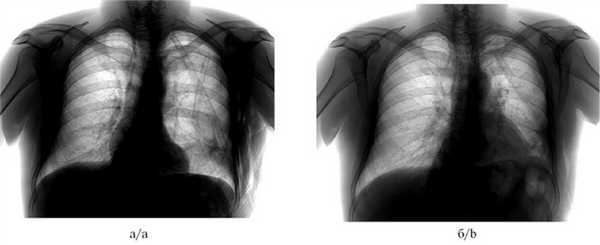

Рис. 2. Рентгенограммы органов грудной клетки пациента до (а) и после (б) выполнения окклюзии бронха.

а — пневмоторакс слева, подкожная эмфизема левой половины грудной клетки, б — через 2 сут после окклюзии, пневмоторакс разрешен, подкожная эмфизема не определяется.